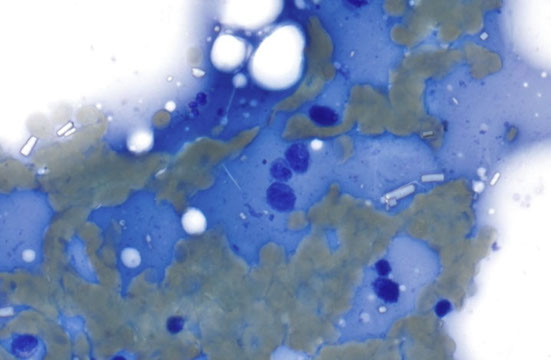

Hematogone hyperplasia - blue circles: hematogones; pink circles - mast cells [4]

Hematogone hyperplasia

Seen post chemotherapy, post stem cell transplant, immune thrombocytopenic Purpera, Copper deficiency, viral infections, metastatic malignancy

Flow immunophenotype: Dim variable city 45 Very low to low side scatter CD10+, CD19 +

- Partial dim CD20 - Partial CD34 and TdT